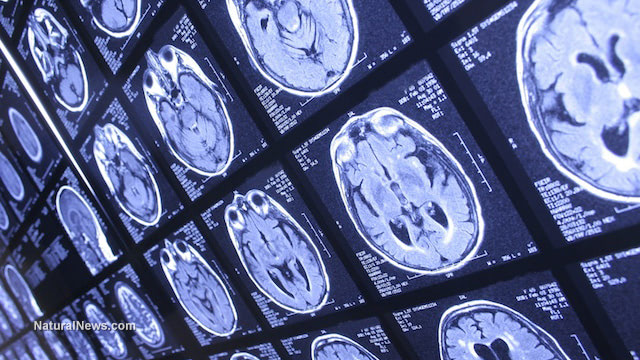

The recent study was only one in many research that established a correlation between lead exposure and adverse neurologic conditions. Lead exposure in childhood was tied to permanent brain damage in adulthood, a 2009 study found. Researchers pooled data from the Cincinnati Lead Study and examined 33 adults who were part of the original cohort who had high lead exposure in infancy and childhood. According to the study, the participants showed histories of low IQ, juvenile delinquency, and criminal arrests. Data from functional magnetic resonance imaging tests showed that the participants needed to stimulate additional brain regions in order to complete two tasks designed to assess the brain’s executive functioning. (Related: Lead exposure linked to emotional problems, anxiety and pervasive developmental problems in children.)

“This tells us that the area of the brain responsible for inhibition is damaged by lead exposure and that other regions of the brain must compensate in order for an individual to perform. However, the compensation is not sufficient. Many people think that once lead blood levels decrease, the effects should be reversible, but, in fact, lead exposure has harmful and lasting effects,” explained lead author Kim Cecil on Science Daily.

The results were presented at the annual meeting of the Radiological Society of North America.